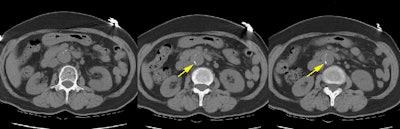

Type A Dissection:

The non-contrast CT examination revealed displacement of intimal calcifications consistent with a dissection (yellow arrows)